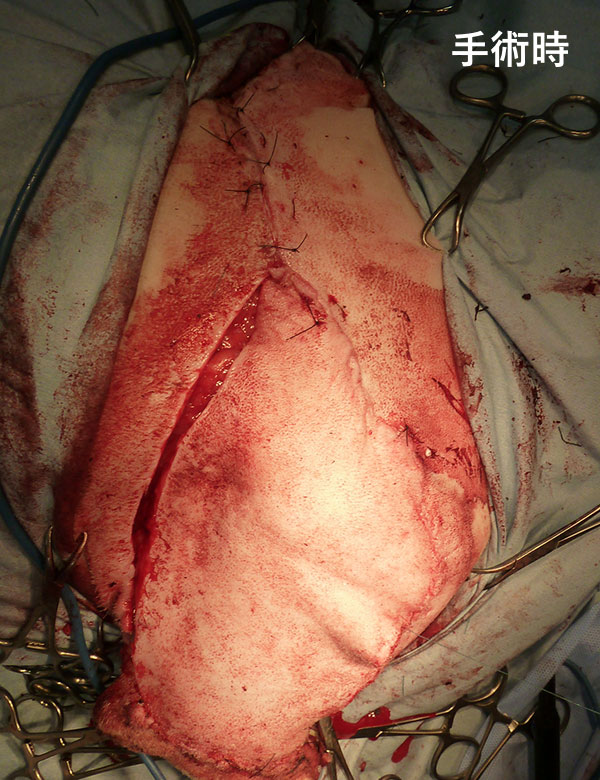

術式:胸胸動脈皮弁術

手術後、皮膚移植した部位はごく一部で回復が遅れたものの問題なく傷は回復しました。手術後の病理組織検査では、取り残しもない完全切除であったため、当初の目的である完全切除と機能温存が達成されました。ワンちゃんによっては、移植部位の毛の色や走行が周囲と異なるため、手術部位が目立つこともあります。